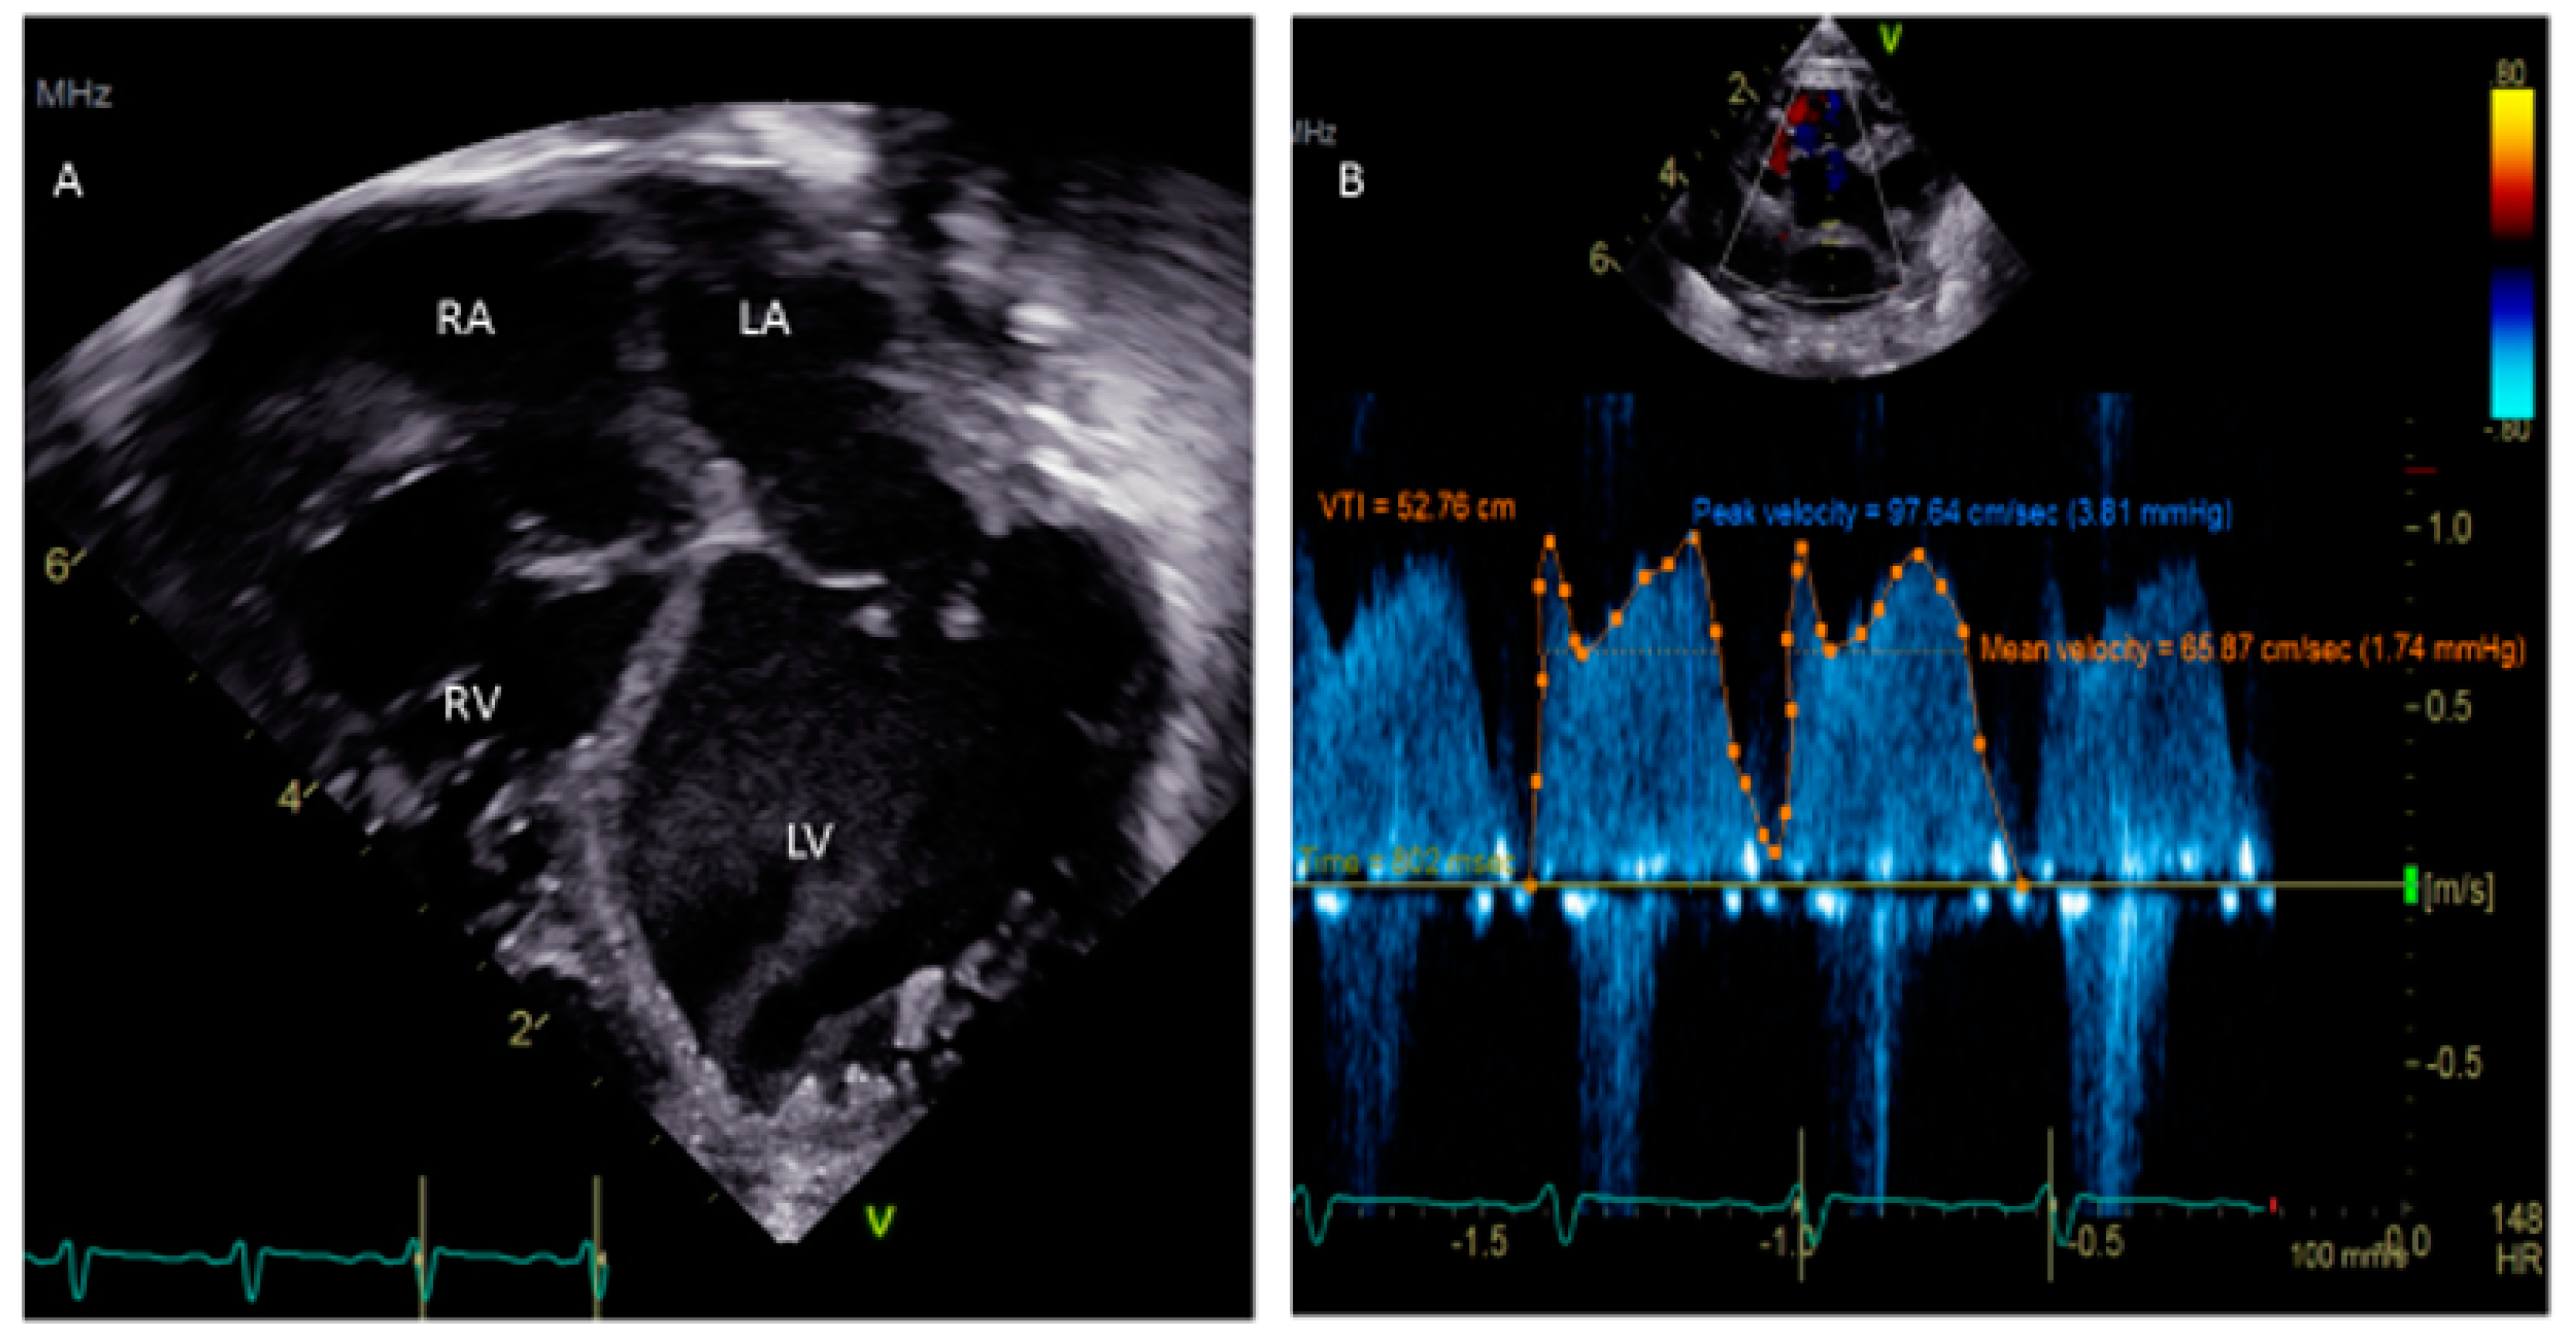

- Silvestry, F.E. Guidelines for the echocardiographic assessment of atrial septal defect and patent foramen ovale from the American Society of Echocardiography for cardiac angiography and interventions. J. Am. Soc. Echocardiogr. 2015, 28, 910–985. [Google Scholar] [CrossRef]

- Mojadidi, M.K.; Robets, S.C.; Winoker, J.S.; Romero, J.; Goodman-Meza, D.; Gevorgyaan, R.; Tobis, J.M. Accuracy of transcranial Doppler for the diagnosis of intracardiac right to left shunt: A bivariate meta-analysis of prospective studies. JACC Cardiovasc. Imaging 2014, 7, 236–250. [Google Scholar] [CrossRef] [PubMed]